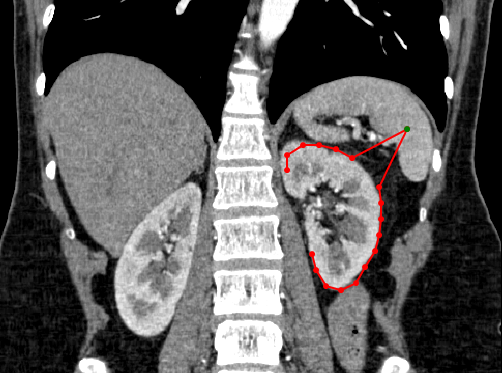

» Create curve- simple click on the starting position of interest and then continue to click along the path of interest. A continuous line will be created between each clicked point and a circle will be shown for each click that was conducted. To finish the curve, simple double click using the mouse.

» Adjust curve– To adjust the shape of the curve, simple select one of the points shown along the curve and drag it to the new position of interest

» Panorama mode- creates resultant image taking all views into account when curve is drawn (panorama mode is only accessible in the curved MPR mode).